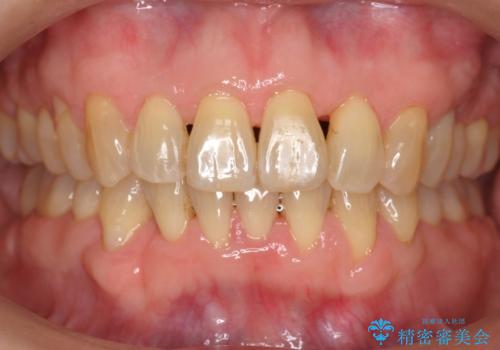

前歯のがたつき インビザラインで抜歯矯正

右下の犬歯の1本抜歯で最小限の抜歯で並べることができました。

奥歯も上下交互になるようにかみ合わせることができました。